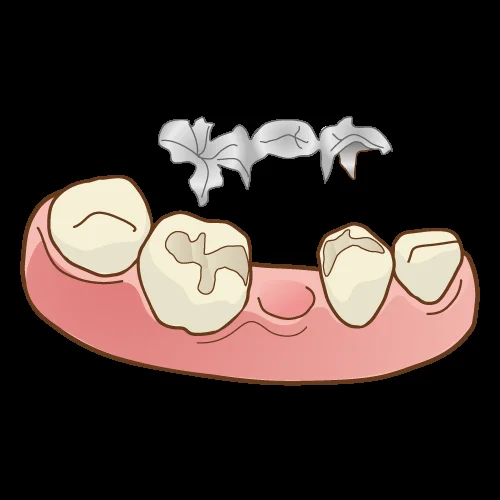

インレー形態のみで作成するブリッジの事をインレーブリッジと言います。

こういう感じですね。

特にブリッジの場合は、出来たものを入れるため、アンダーカットが出来ないように前後の歯の平行性を合わせる必要があります。